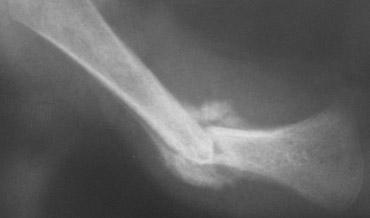

Gãy xương góc (Corner fracture)

Gãy xương góc hành xương, còn được Kleinman gọi là tổn thương hành xương kinh điển, lần đầu tiên được mô tả bởi Caffey, người đã ghi nhận những gãy xương đặc biệt này ở trẻ em có tụ máu dưới màng cứng. Chúng thường xuất hiện hai bên và ở đầu dưới xương chày, thường gặp hơn ở phía trong.

Khi một mảnh xương nhỏ bị bong ra do lực cắt tác động lên sụn tăng trưởng mỏng manh, nó được nhìn thấy như hình ảnh gãy xương góc điển hình. Những gãy xương này phổ biến nhất ở xương chày, đầu dưới xương đùi và đầu trên xương cánh tay. Chúng thường xuất hiện hai bên.

Những gãy xương này thường rất kín đáo, và khả năng phát hiện phụ thuộc trực tiếp vào chất lượng của các nghiên cứu hình ảnh.

Chính vì lý do này, khảo sát xương toàn thân trong các trường hợp nghi ngờ lạm dụng trẻ em phải được thực hiện với sự chú ý tối đa đến chất lượng phim chụp.

Gãy xương kiểu tay xách xô (Bucket handle fractures)

Gãy xương kiểu tay xách xô về bản chất giống với gãy xương góc.

Mảnh xương bị bong ra có kích thước lớn hơn và được nhìn thấy theo hướng “en face” (nhìn thẳng) như hình đĩa hoặc tay xách xô.

Hình ảnh

Gãy xương kiểu tay xách xô ở đầu trên xương chày. Mảnh gãy hành xương được nhìn thấy như hình đĩa hoặc tay xách xô.